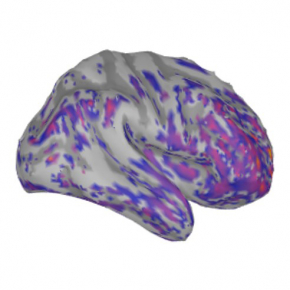

© Andry Andrianarivelo et Peter Vanhoutte - Laboratoire Neuroscience Paris-Seine (CNRS/Sorbonne Université/Inserm)